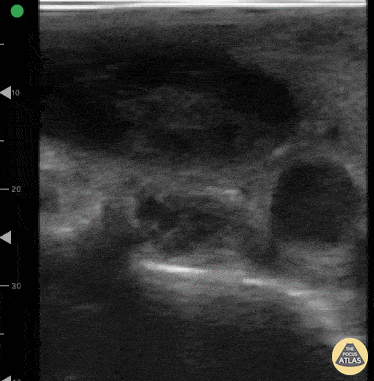

Vérifier si les voies urinaires hautes sont obstruées (colique néphrétique).

Points clés :

- Repérage des loges rénales en coupes longitudinale et transversale.

- Différenciation entre le sinus rénal hyperéchogène et le parenchyme.

- Identification de l'anéchogénéité des calices et du bassinet dilatés.

- Comparaison systématique avec le rein controlatéral.

- Mise en garde face aux pièges : pelvis extrarénal ou kystes parapelviens (diagnostics différentiels).